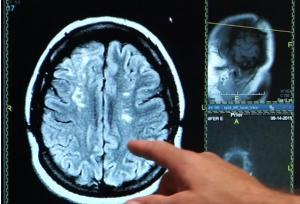

Une supplémentation en calcium va réduire le flux sanguin vers le cerveau et favoriser le développement de la démence vasculaire chez les personnes à risque déjà élevé ou à antécédent d'AVC, explique cette étude, publiée dans la revue Neurology. Des résultats à confirmer mais qui incitent à rediscuter d’une telle supplémentation avec son médecin traitant et à préférer l’apport alimentaire en cas de besoin particulier en calcium.

Les chercheurs de l'Université de Göteborg (Suède) et de l'University College London ont suivi durant 5 années, 700 femmes âgées de plus de 70 ans, exemptes de démence, dont 98 prenaient des suppléments de calcium. Au cours du suivi, ces participantes ont subi des tests d'imagerie afin de détecter les signes de maladie cérébrovasculaire, des lésions de la substance blanche ou les zones du cerveau ayant une mauvaise circulation sanguine- ce qui est associé à la démence vasculaire. Au cours du suivi,

La supplémentation en calcium déclencheur d'AVC chez les femmes déjà à risque élevé : Enfin, une analyse plus poussée montre que la prise de calcium n'a pas augmenté le risque de démence chez les femmes qui avaient pas eu d'AVC ou qui ne présentaient aucun signe de lésions de la substance blanche sur leurs scans du cerveau. L'analyse révèle que l'augmentation du risque de démence est concentrée chez les femmes sous supplémentation, à antécédents d'accident vasculaire cérébral, ou présentant déjà des signes de dommages aux vaisseaux sanguins dans le cerveau. Les résultats de cette étude observationnelle, mené sur un petit échantillon de femmes sous supplémentation, doivent être confirmés. Les chercheurs concluent ainsi : « La supplémentation en calcium peut augmenter le risque de démence chez les femmes âgées ayant une maladie cérébrovasculaire ». Cependant ces résultats alertent, une nouvelle fois, sur l'importance de discuter de telles supplémentations, qui ne sont pas anodines, avec le médecin traitant.